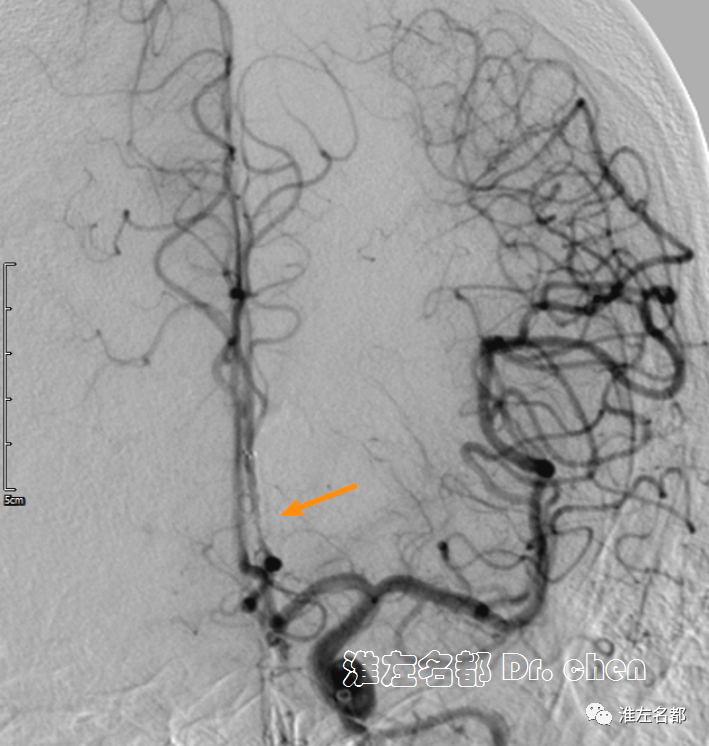

△头颅CTA:左侧大脑前动脉A2段远端闭塞(橙箭)。

△颈部CTA:左侧颈内动脉颅外段螺旋样延长迂曲(白箭)。

△颅脑CTA:左侧大脑前动脉A3段狭窄(橙箭),但前向血流可。

△颅脑CTA:左侧大脑前动脉管腔通畅,未见明显狭窄。